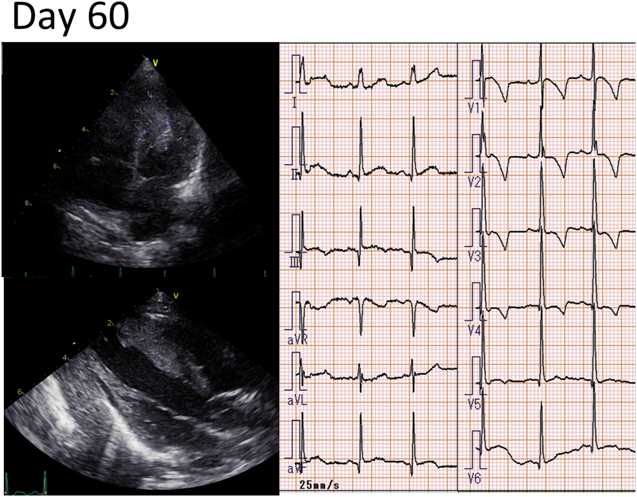

Fig. 3 Echocardiography and electrocardiography at 60 days of age

Echocardiography shows that the right and left ventricle cardiac tumors are almost one-quarter of the original sizes, and there is no obstruction of the inflow and outflow tracts. On electrocardiography, there is no low ST level or negative T wave. QTc=390 ms (slightly shortened).